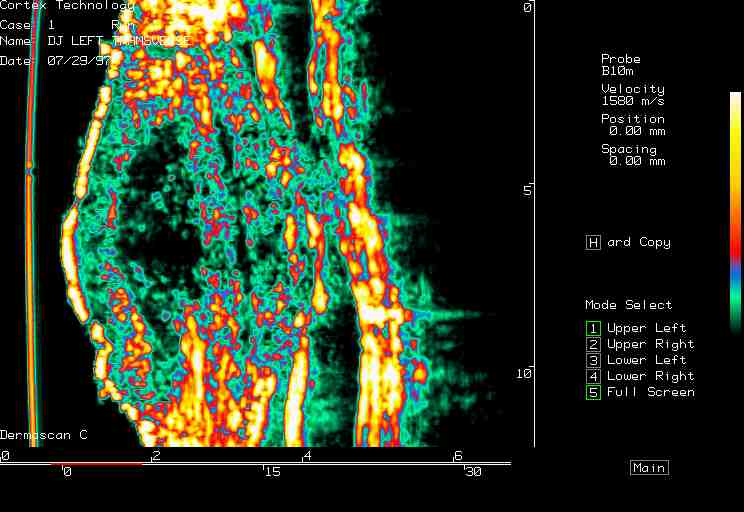

20 MHz 2D images

| Reactions |  Irritant reaction |

Patch test, back |

Insect bite |

Allergic reaction |